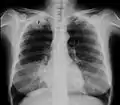

Der Pancoast-Tumor (synonym apikaler Sulkustumor) – benannt nach dem Erstbeschreiber, dem US-amerikanischen Radiologen Henry Pancoast – ist ein rasch fortschreitendes peripheres Bronchialkarzinom im Bereich der Lungenspitze (Apex pulmonis) beziehungsweise der oberen Lungenfurche, welches relativ rasch auf Rippen, Halsweichteile, Armgeflecht und Wirbel übergreift. Daher wird dieser Tumor auch als „Ausbrecherkrebs“ bezeichnet.